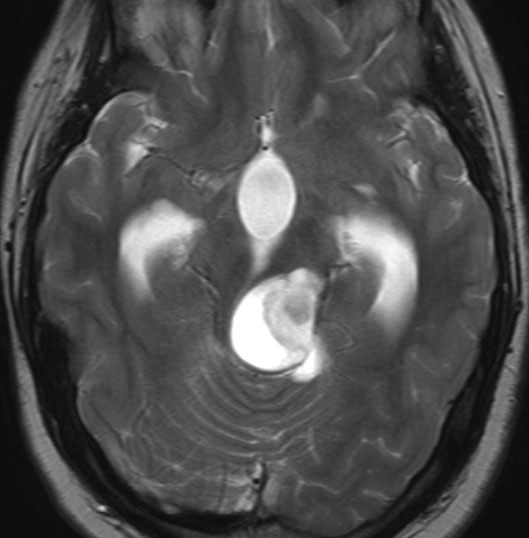

19歳で偶然見つかった例

頭部打撲で検査され偶然発見された19歳男性ものです。中脳視蓋全体が腫大して腫瘍化しています。左側にのう胞があり周囲が淡くガドリニウムで増強されます。

中脳水道の癒着閉塞により,高度の停止性水頭症になっています。高身長ですが頭囲が61cmありました。小さい頃から頭が大きいので家族も気にならないようです。数年以上あるいは10年近くの長期にわたってこの水頭症は変わらないのでしょう。

頭痛などの症状はなく,眼底所見も視神経乳頭の異常はありませんでした。無治療で経過観察をしています。認知機能も全く正常で,国立大学から大学院に進む予定です。

もちろんこれからも注意深く経過観察する必要があります。